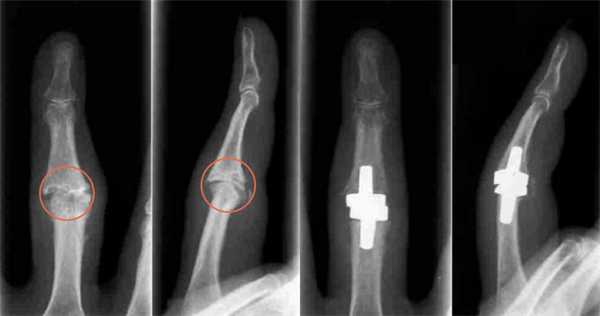

Эндопротезирование проксимального межфалангового сустава кисти

Эндопротез проксимального межфалангового сустава представляет собой несвязанный эндопротез, состоящий из проксимального и дистального компонентов. Материалом изготовления служит циркониевая керамика.

- Идиопатические и посттравматические артрозы;

- Дегеративные и постинфекционные артрозы;

- Костный анкилоз;

- Неправильное положение (вследствие артроза, травмы);

Эндопротезирование пястно-фалангового сустава кисти

Эндопротез пястно-фалангового сустава представляет собой несвязанный эндопротез, состоящий из проксимального и дистального компонентов. Материалом изготовления служит циркониевая керамика.

- Дегенеративные и постинфекционные артрозы;;

- Костные анкилозы;